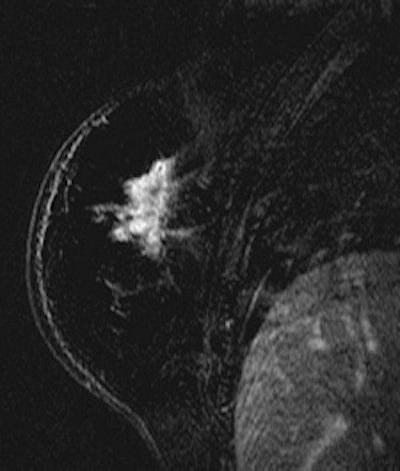

![]() ![]() |

| Patient with breast cancer (invasive ductal carcinoma, grade II). MR-subtracted images (three minutes after contrast medium injection) before (left) and at the end (right) of the neoadjuvant chemotherapy. Initial staging: unifocal infiltrating cancer. After treatment, even if there is a decrease in size of the cancer, its long axis (RECIST) is unchanged with a multifocal shrinkage of the tumor. Unsuccessful first breast-conserving surgery, then mastectomy. Image courtesy of Dr. Anne Tardivon. |